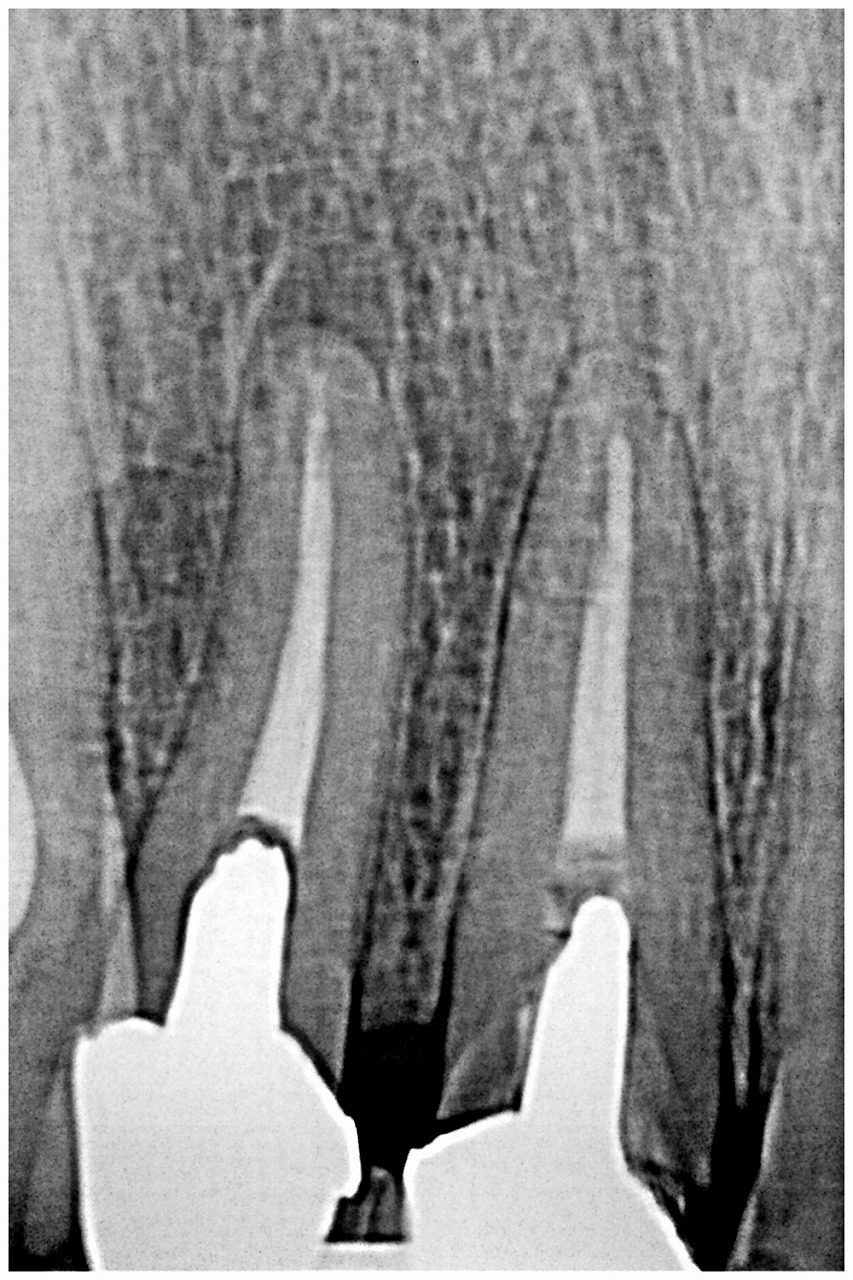

前歯部の抜歯後、ブリッジかインプラントか? インプラントになりました|お知らせ |広島市安佐南区の歯科医院 前歯部の抜歯後、ブリッジかインプラントか? インプラントになりました トップ お知らせ・ブログ お知らせ 前歯部の抜歯後、ブリッジかインプラントか? インプラントになりました 前歯部の抜歯後、ブリッジかインプラントか? インプラントになりました 右上がこのように連結してありました デンタルレントゲンにて 連結部もグラグラでひっおあるとすぐに外れてきました 中は黒く、柔らかく状態はかなり悪かったです 頬側の歯質も破折して飛んでなくなっていました 仮歯を作成していきました まずは仮歯を入れていきました これよりインプラント希望のため抜歯即時インプラント埋入を行っていきます Web診療予約 初めての方へ 選ばれ続ける理由 院内設備について 歯が痛いしみる一般歯科 歯がぐらぐらする歯周病 健康な歯を保ちたい予防歯科 子供の虫歯予防をしたい小児歯科 銀歯をセラミックに審美歯科 白い歯を目指しませんか?ホワイトニング 矯正専門医がいるので安心矯正歯科 抜けた歯を補いたいインプラント・入れ歯 医院案内 スタッフ紹介 メリィハウス歯科クリニックオフィシャルホームページ ラベンダー歯科クリニックオフィシャルホームページ お知らせ・ブログ ホーム 診療科目 一般歯科 歯周病治療 予防治療 小児歯科 審美治療 ホワイトニング 矯正歯科 入れ歯・インプラント マウスピース矯正 初めての方へ 院長・スタッフ 設備紹介 医院案内・アクセス メニューを閉じる